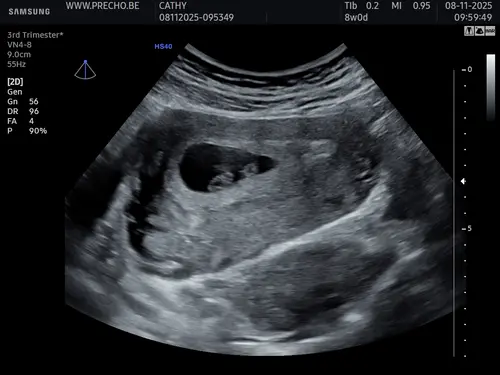

Deze beter misschien?

Dan doe ik ook maar mee, wat denken jullie bij die van mij. Is inwendige echo

Uitwendig! Sorry vergeten te benoemen

CHATGPT zegt met deze uitwendige echo een meisje, wat denken jullie? Ik heb ...

Ja heel lastig lijkt het maar je moet eigenlijk naar de ligging / locatie van je placenta kijken. Ik denk ook een meisje馃┓